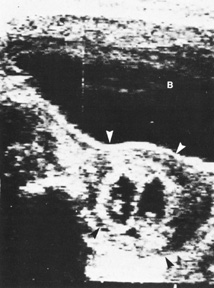

Traditional genetic amniocentesis is usually offered between 15 and 20 weeks' gestation. Amniocentesis performed earlier has a higher complication rate, as well as more amniotic culture failures. It may be offered when prenatal maternal screening results are high risk for a genetic abnormality or as an elective diagnostic test such as in advanced maternal age or prior history of an aneuploidy (see Fig. 2).

Fig. 2. Left midabdomen of neonate shows indented area probably resulting from contact of the amniocentesis needle with the abdominal skin.

Many large, multicenter studies have confirmed the safety of genetic amniocentesis, as well as its cytogenetic diagnostic accuracy (greater than 99%).2 The fetal loss rate is approximately 0.5%, and minor complications occur infrequently. Table 4 lists known complications for amniocentesis.

Needle injury rare (Fig. 2)